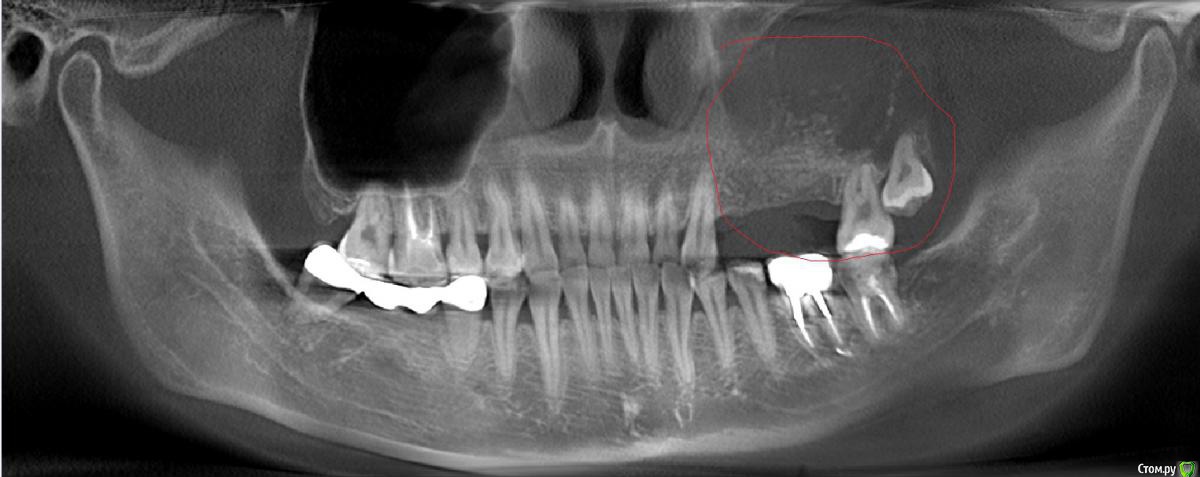

Jin Опубликовано 7 сентября, 2018 Поделиться Опубликовано 7 сентября, 2018 Добрый день, уважаемые врачи!Позвольте проконсультироваться в отношении тактики лечения.В стоматологической клинике в феврале удаляли три зуба для последующей имплантации. Фрагмент корня зубы в пазухе спровоцировал гайморит с яркими симптомами.В марте этого года была проведена операция по удалению фрагмента корня зуба в левой гайморовой пазухе. Комбинированная операция совместно с ЛОР и ЧЛХ хирургами в условиях стационара. Расширили соустье в носу. Доступ обеспечен через десну в верхней челюсти носовое отверстие.В конце августа проведен синус-лифтинг с установкой мембраны. Через полторы недели почувствовалось недомогание и боли в глазу. Снимок показал перфорацию мембраны и миграцию материала (биоосс?) в гайморову полость. ЛОР при попытке промыть отверстие через соустье в носу не смог дренировать гнойные массы (загустение?). Назначил капельницы с антибиотиками и антигрибковыми препаратами, чтобы снять воспаление, разбавить гнойные массы и в дальнейшем попытаться промыть пазухи в несколько этапов. На снимке отчетливо видна разгерметизация полости с костным материалом, распределенным по всей полости. Прошло не более недели после синуслифтинга. Насколько благоприятен прогноз при таком лечении и стоит ли на него рассчитывать? Может, решить проблему хирургическим способом? Ведь при промывании костный материал и дальше будет выходить в полость?Либо врач считает, что возможно сохранить материал, полость может загерметизироваться? Или в таком случае все скиснет? Опасаюсь, что повторный синуслифтинг будет еще более неблагоприятным либо невозможным. Врач опытный и авторитетный, склонен доверять ему, так как он старается провести все наименее травматично.Спасибо заранее. Ссылка на комментарий

Jin Опубликовано 7 сентября, 2018 Автор Поделиться Опубликовано 7 сентября, 2018 Сарказм принят. Тут вопрос не в доверии. Просто когда ты делаешь операцию в одной и той же области, и это не удаление бородавки, а последствия ощущаешь на себе в виде букета симптомов острого гайморита, хочется для спокойствия заручиться поддержкой нескольких компетентных мнений, прежде чем делать что-то радикальное. Врач имеет право на ошибку, разве нет? Ведь именно для таких целей и придумали консилиумы, этот портал наконец.)))Страшно снова попасть на новые осложнения. Синус не железный.(((Снимок прилагаю. Ссылка на комментарий

kamranchick Опубликовано 7 сентября, 2018 Поделиться Опубликовано 7 сентября, 2018 В пазухе что то явно не очень все хорошо... Ссылка на комментарий

Irouil Опубликовано 8 сентября, 2018 Поделиться Опубликовано 8 сентября, 2018 Надо пробовать сохранять графт, сначала нужно отдренировать пазуху, доступ через нос. Надо КТ сделать чтобы убедиться на 100%, но создаётся впечатление, что естественное соустье не справляется с оттоком, его надо расширять. В таком случае все можно сделать за одну хирургию под эндоскопическим контролем. 1 Ссылка на комментарий